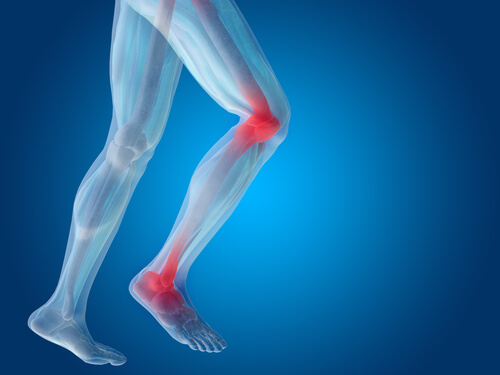

Es fundamental prestarle mucha atención a los cartílagos, ya que es un tejido que, una vez dañado, es muy difícil que pueda repararse por completo. Esto trae como consecuencia diferentes dolencias, entre ellas la artritis. Los esguinces son las habituales lesiones de este soporte. Las zonas más afectadas son:

Tobillos

Rodillas

Es vital que los cartílagos se mantengan saludables, sobre todo los de las rodillas, que son los que sostienen más peso (de casi todo el cuerpo). Los síntomas más habituales de lesión o daño son: